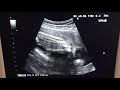

Когда чихаю при беременности писаюсь. Это одно из распространенных явлений, с которыми сталкиваются многие женщины во время беременности. Изменения, происходящие в организме в этот период, могут оказывать давление на мочевой пузырь, что может вызывать неконтролируемое покапывание мочи при чихании или кашле.

Причина этого явления заключается в ослаблении тазового дна и мышц мочевого пузыря под воздействием гормонов, отвечающих за беременность. Эти гормоны позволяют растянуться тканям и связкам, чтобы сделать место для растущего плода. Ослабление мышц может привести к снижению контроля над сочленениями и органами тазового дна.